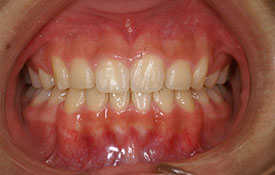

叢生|ブラケットを用いた治療

CASE 1

CASE 2